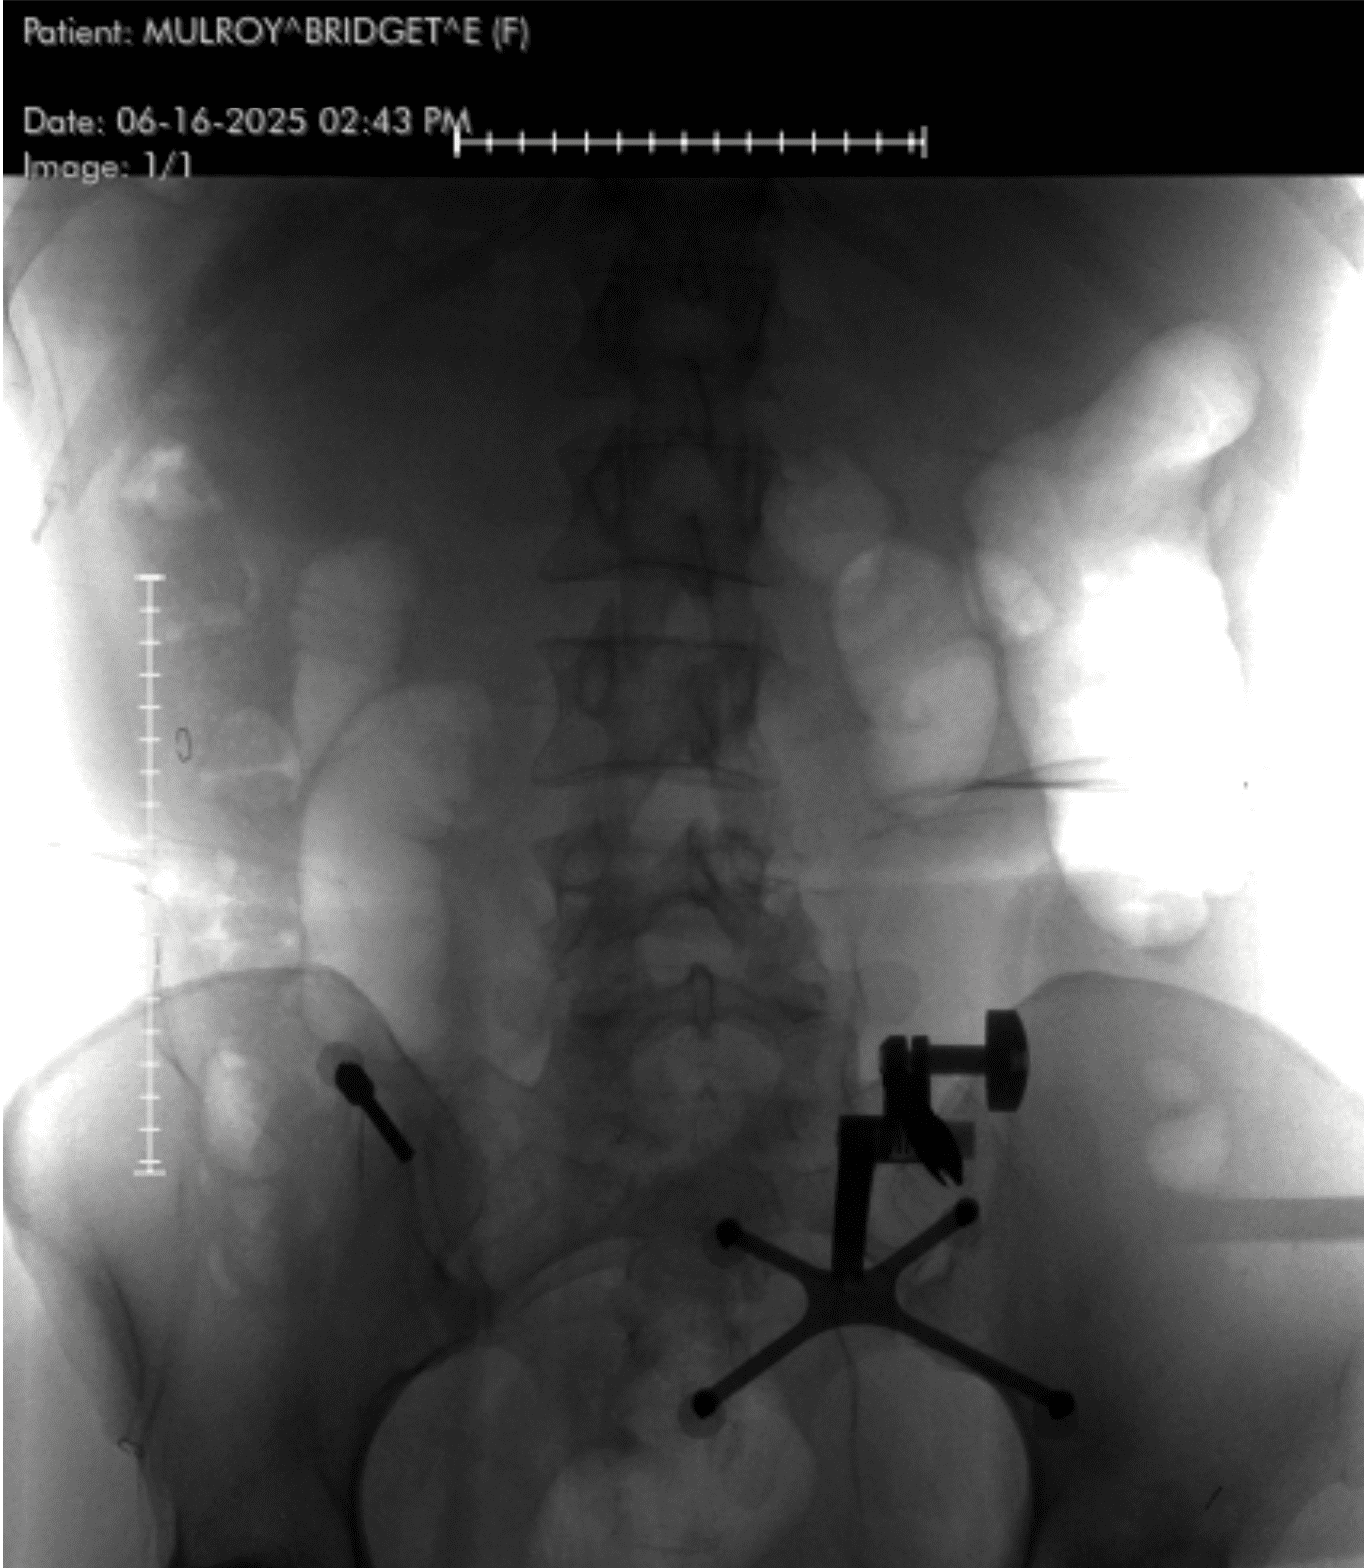

Image Credit: Bridget Mulroy

Instead of using an external brace, Dr. Lopez used hardware—screws and rods—to create internal support.

“Technically, you didn’t have a spinal fusion,” he clarified. “You had spinal instrumentation and stabilization. A fusion requires bone grafts and biologic processes to encourage new bone growth.”

He performed a minimally invasive posterior lumbar instrumentation from L2 to L5. That means he made small incisions guided by real-time navigation using a machine called the O-arm—a rotating intraoperative CT scanner. A localizing pin in my pelvis communicated with a computer, which told him exactly where to place each screw.

“Once the screws are inserted,” he explained, “I use an X-ray to place the rods. The key decisions involve knowing which levels to include, ensuring screw trajectory is perfect, and having a plan if something doesn’t go right.”

A Future Built on Titanium—and Hope

I asked him what becomes of all the hardware—the screws, rods, and implants—once the spine heals.

“They support the body through the healing process,” he said. “Once bone growth stabilizes the segment, it’s like the hardware isn’t even there. But if a surgery doesn’t heal properly, the hardware can become loose, break, or even get infected.”

“There is some nuance here with the terminology. You underwent a spinal instrumentation and stabilization without a fusion. I used hardware to essentially “brace” your spine from the inside (as opposed to an external brace which would not have worked in this case). A spinal fusion requires biologic assistance from the body in addition to stabilization of the segment. That would mean using bone graft and carpentry work to the bone that would facilitate signaling pathways that calls bone cells to the area to form more bone. Spinal fusions are typically required in instances where we are removing bone and know that we are going to de-stabilize a segment in the process, when we are attempting to change the shape of the spine and want it to heal in that new position, or when there is a severe pathology that needs new bone to form to fully stabilize the segment in the long term.”

“The process behind a posterior instrumentation with stabilization is as follows (I did this minimally invasive so it’s slightly different): I placed a metal localizing pin into your pelvis which talks to the computer in the room which helps us with real time screw navigation. We spin a large machine called an O-arm which performs in intraoperative CT scan which gives us a lot of information about your bones. We use that as a real time navigation for placing the screws into the bones. We then used a special marker to know exactly where to place your incisions based on the real-time feedback from the navigation (we can keep the multiple incisions small because of this technology). Once the incisions are made, we dissect down the skin, fascia, muscle, and down to the bones of the spine. From there I use the real-time navigation to understand the trajectory of the screw and place each one with a set of instruments—first an awl to make a small hole in the bone, then a tap to widen that hole a bit in order to better facilitate screw insertion, then the actual screws. Once the screws are inserted, I use an x-ray machine to help me place the rods. The real decision making here includes the pre-operative planning and knowing which levels to include, the proper screw trajectory and to know if the feedback from the live navigation is accurate, and what to do if a screw isn’t perfect.”